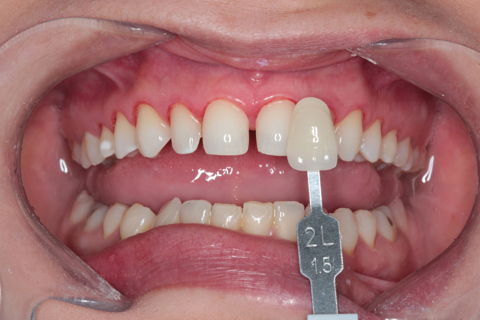

Tomada de cor - Substrato

4º Passo: Preparo minimamente invasivos + Moldagem + Tomada de cor do substrato e envio ao Laboratório MW Dental Studio para confecção dos laminados cerâmicos.